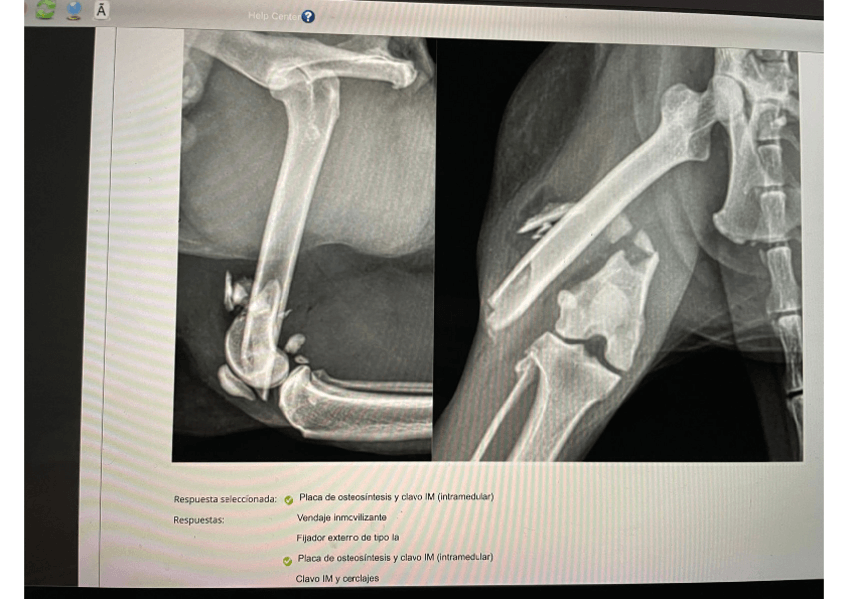

Exámenes - EXAMEN-CACII-RESUELTO-TRAUMA-Y-ONCO.pdf

Exámenes - Examen-Modulo-2- 2023 CORREGIDO-RESPONDUS.pdf

Exámenes - Examen-Modulo-1 2023-NAC-y-UCI-RESUELTO.pdf

Exámenes - Trauma-Exam-2020-UPDATED-2.pdf

Exámenes - EXAMENES-RESUELTOS-CAC-II-MOD2.-TRAUMA-Y-ONCO.pdf

Exámenes - Examan Trauma.pdf

Exámenes - Examen-Traumatologia-Oncologia-Junio-2024.pdf

Exámenes - EXAMEN-TRAUMA-Y-ONCO-ABRIL-2024.pdf